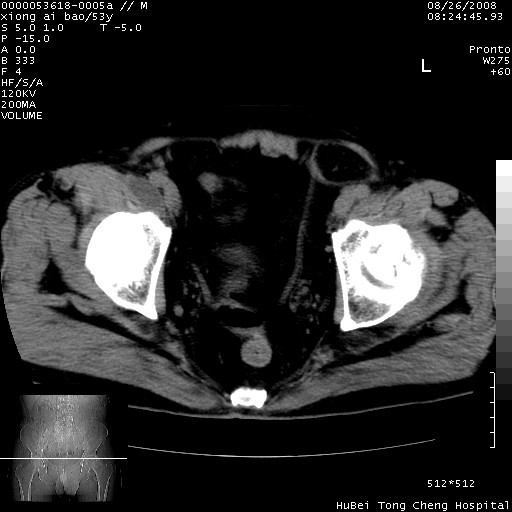

标题: CT15583:M,53Y。请老师指教分析骨盆及其他病变。 [打印本页]

标题: CT15583:M,53Y。请老师指教分析骨盆及其他病变。

股骨头坏死/腹股沟疝。

双侧股骨头无菌坏死,左侧腹股沟斜疝。

非常典型病例,双侧股骨头坏死伴双髋关节周围软组织肿胀,左腹股沟疝。

双侧股骨头坏死伴双髋关节周围软组织肿胀,左腹股沟疝。

双侧骨股头无菌性坏死,左侧腹股沟疝

双侧髋关节肿胀明显,感觉还不能排除结核。

考虑双侧髋关节结核,左侧腹股沟疝